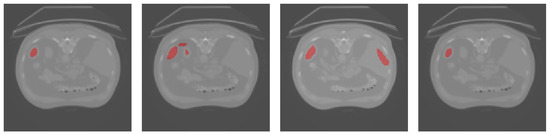

3.1. Results Obtained on the Brain MRI Dataset

| Dice | TPR | TNR | HD95 | |

|---|---|---|---|---|

| U-Net | 54.35% | 45.23% | 99.80% | 9.22 |

| UNet++ | 56.45% | 48.35% | 99.76% | 8.06 |

| Att-UNet | 58.06% | 46.87% | 99.86% | 8.35 |

| Focus-UNet | 48.59% | 37.34% | 99.85% | 9.43 |

| SAB-Net | 61.83% | 55.15% | 99.78% | 8.06 |